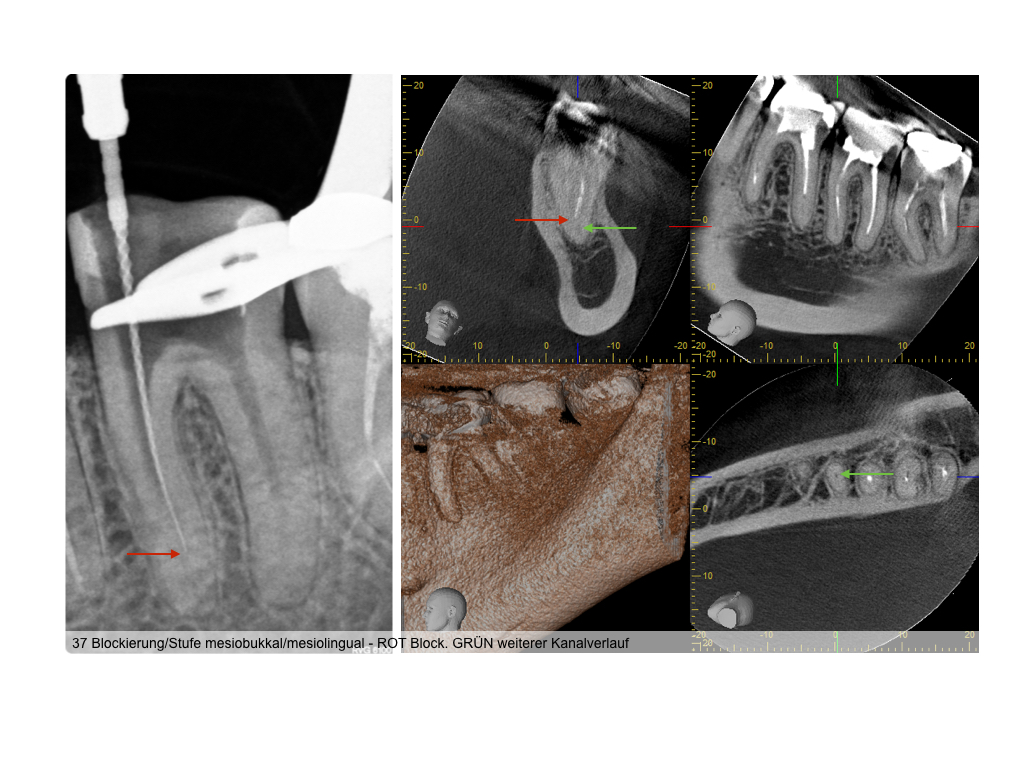

wsi-122016-015

4 auf einen Streich (2)